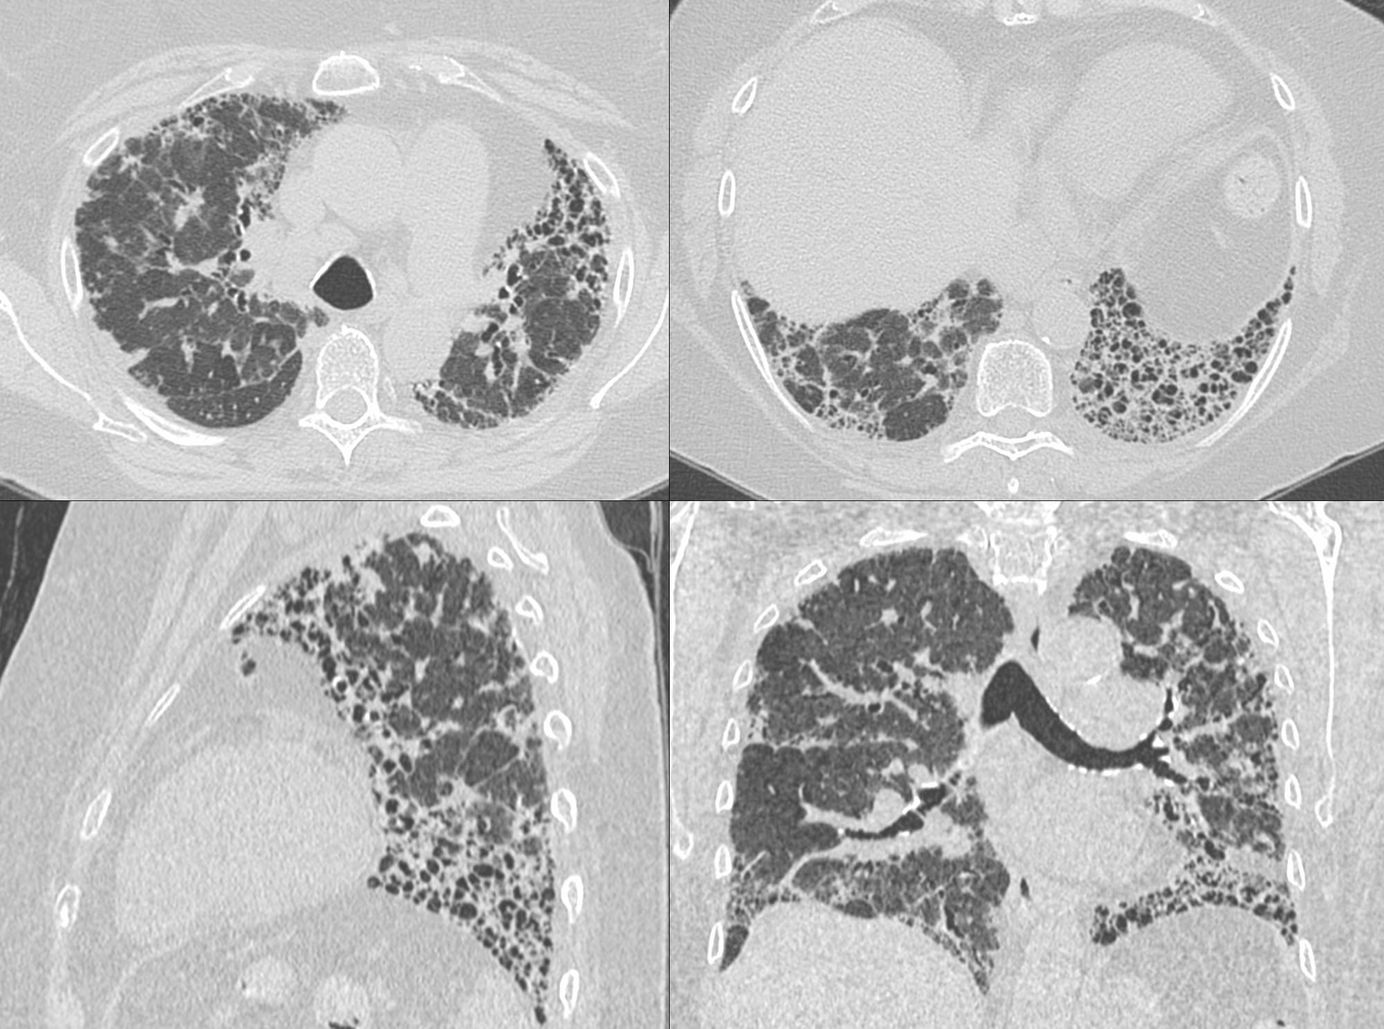

Case of the Day 116 - Mixed Patterns in Connective Tissue Disease ILDs Members Public

Mixed patterns are increasingly being recognized in CTD ILDs and should be mentioned in the report.